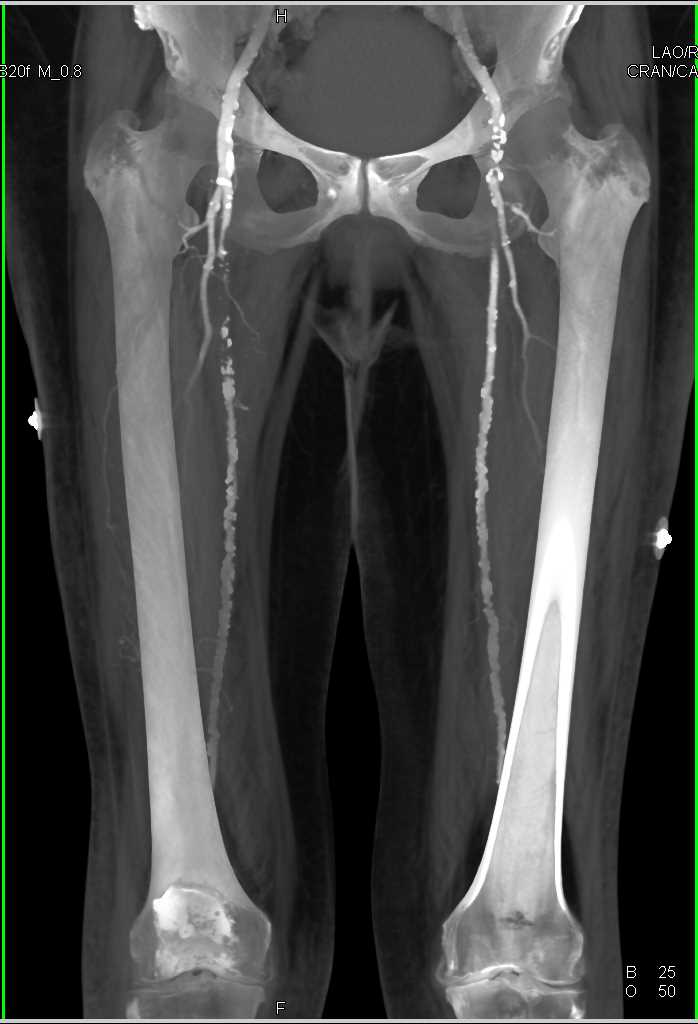

Stabwound Without Active Extravasation of Contrast